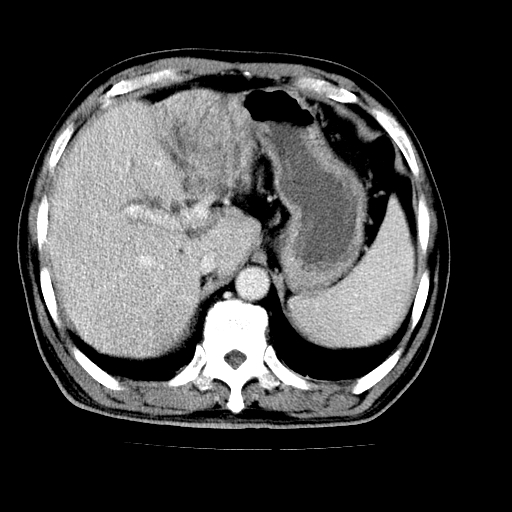

男,66岁,上腹部不适、黄染一周。彩超示:肝左叶占位,肝内胆管扩张,胆总管扩张,胆总管占位?

肝左叶不规则软组织肿块影,边缘不规整邻近肝实质受累分界不清;肝内胆管(左叶)明显扩张成“软藤状”,诊断:肝左叶胆管细胞癌。

肝左叶占位性病变,并胆管扩张,符合胆管细胞癌ct表现,门脉左支受累,左肾囊肿。窗宽太窄了,其他的看不清

左叶胆管细胞癌累及胆总管,门脉左支受侵,慢性胆囊炎胆结石,左肾小囊肿